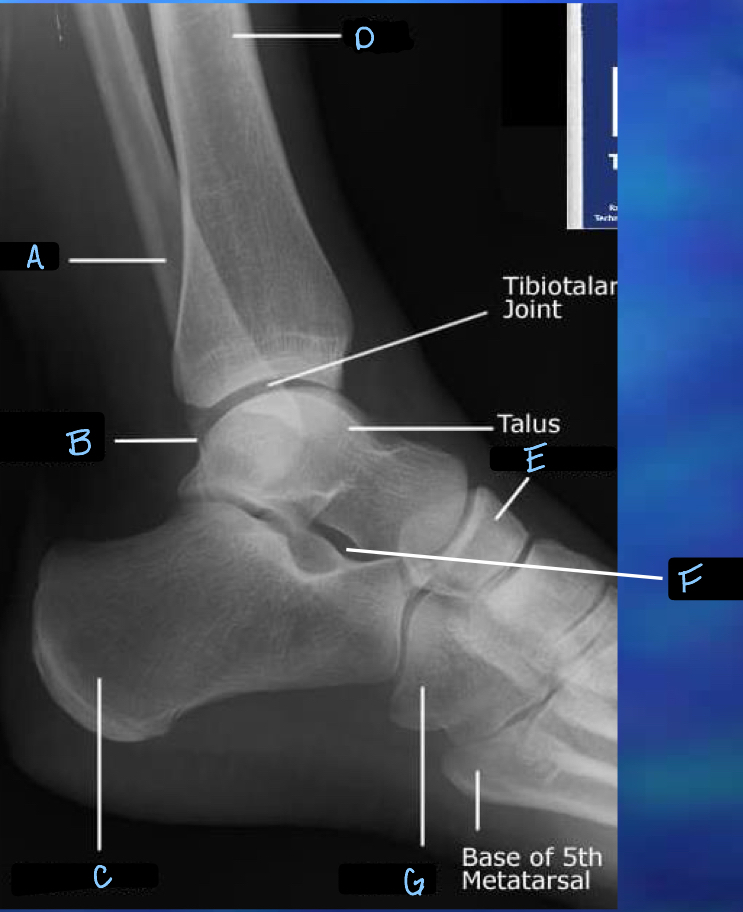

What is A?

tibia

32

What is B?

tibotalar joint

33

What is C?

tarsals

34

What is D?

metatarsals

35

What is E?

phalanges

36

What is F?

sesamoid bones

37

What is G?

navicular

38

What is H?

sinus tarsi

39

What is I?

calcaneum

40

What is J?

fibula